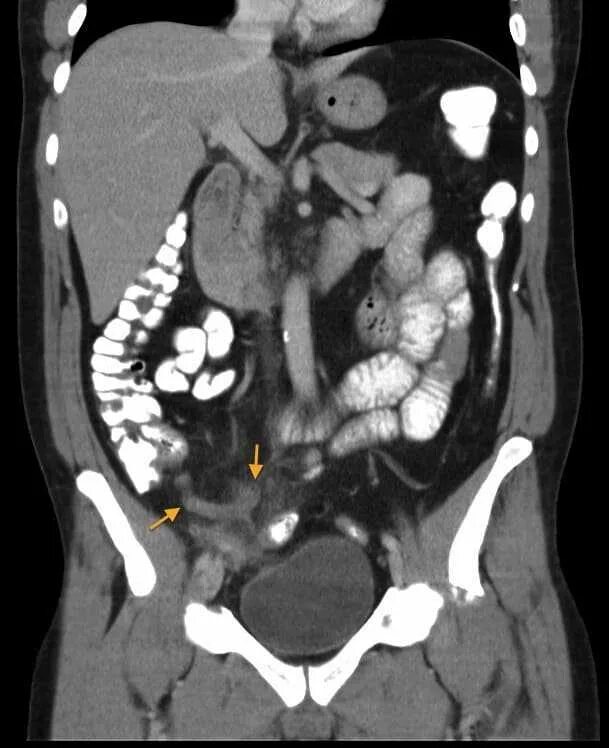

Мрт обп с контрастированием